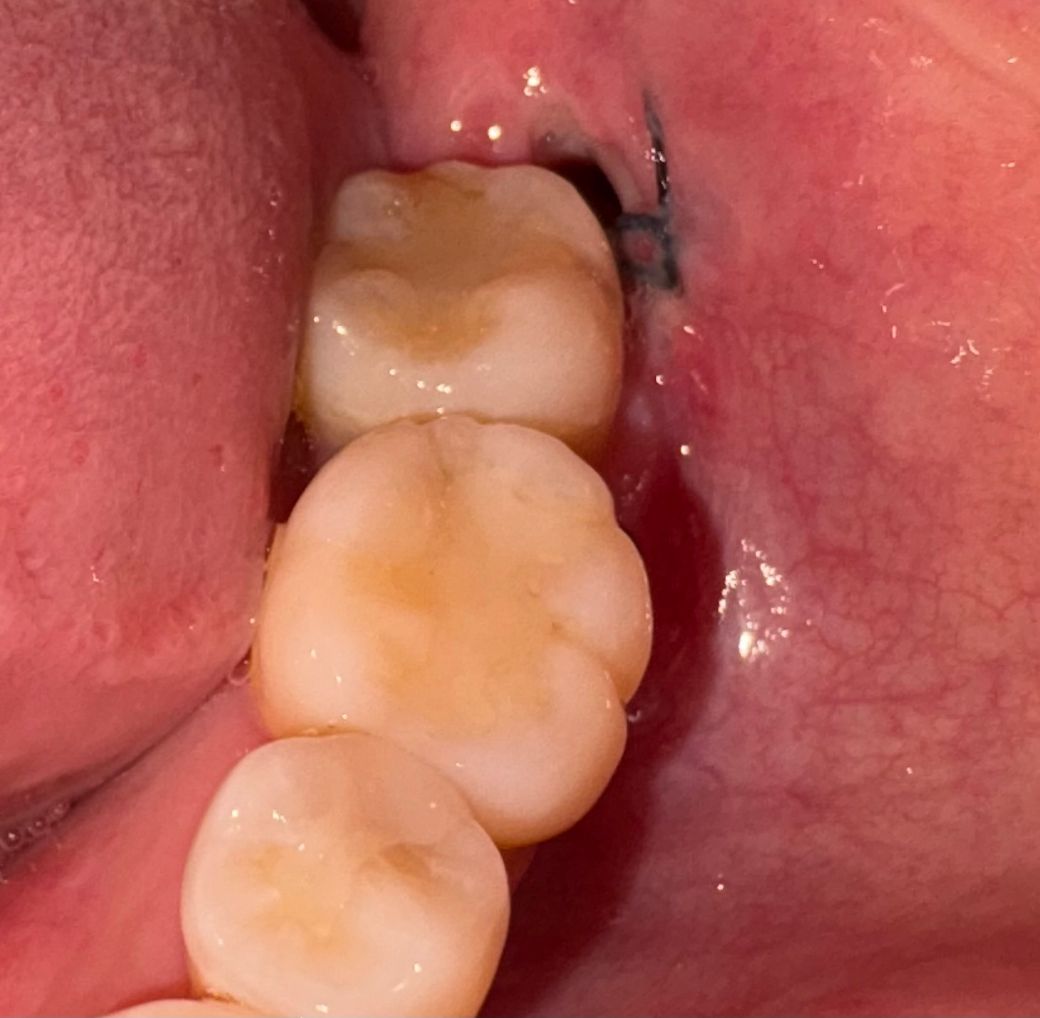

사랑니 발치 6일차 갑자기 구멍이 벌어졌습니다.

첫번째 사진이 오늘 오전 사진이고 두번째 사진은 같은 날 오후 8시쯤 사진입니다. 저녁에 사랑니 부분을 확인하니 전에 없던 구멍이 생겼습니다..

• 1번 째 사진